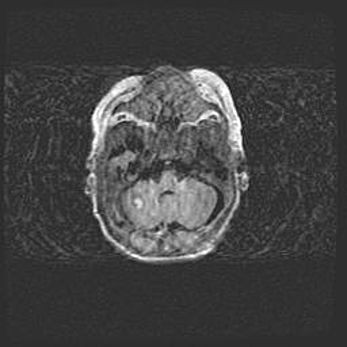

Подострая гематома правой гемисферы мозжечка.

Наружная гидроцефалия.

Возраст: 15 дней

Вес: 3100 г

Пол: женский

Окружность головы: 37 см

Срок гестации: 35-36 недель

При открытой наружной форме гидроцефалии у новорожденных расширяются и переполняются субарахноидные пространства.

Кровоизлияния в мозжечок имеют две клинико-анатомические формы: полушарные гематомы и кровоизлияния в червь.

К появлению этой патологии может привести: повреждения головного мозга, возникающие в результате асфиксии и гипоксии плода при беременности, или травмы во время родов. Редко гематома мозжечка может быть результатом первичной коагулопатии и сосудистой мальформации, диссеминированном внутрисосудистом свертывании, изоиммунной тромбоцитопении.